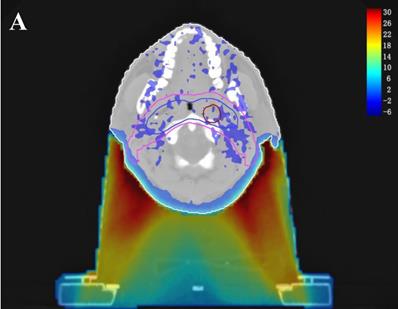

Dose difference distribution map (Plan+ - Plan-)

In the TPS, the results from two plans of the same patient can be directly subtracted to calculate the dose difference distribution map for the patient. As shown in Figure 3, the blue to red gradient represented different absolute dose difference values ranging from -6 Gy to 30 Gy. The dose distribution was dramatically altered due to the attenuation and bolus effect of the immobilization devices. In particular, as shown in B) and C), the neck dose near the head and neck immobilization device was significantly reduced, mainly due to the attenuation when the incident beam ray passes through the immobilization device. Changes in radiation scattering and build-up effect occurred due to the presence of low-density foam in the vacuum pad between the patient's neck and the floor plate. As a result, the dorsal neck skin dose was increased by approximately 10 Gy (Figure 3A, 3B).

Figure 3

Three dimensional dose difference distribution map for a typical NPC case. Dose difference was calculated through subtracting Plan- from Plan+. (A: Cross-sectional plane, B: Sagittal plane, and C: Coronal plane).

The establishment of a virtual model (including geometry and density information) for the treatment couch top within the TPS is a common method used to calculate the attenuation effect of the treatment couch on treatment planning [6,11,12]. In this study, we contoured the head and neck immobilization devices into the external body contour to calculate the immobilization device impact on the dose distribution of NPC IMRT. The density information of the immobilization devices showed the TPS calculation algorithm was able to compute dose for the situation with the immobilization devices enclosed. Due to the attenuation of the immobilization devices, CRs and Dmean in Plan+ were reduced compared to those in Plan- (the prescription dose coverage rates of the four targets were decreased by 1.5-9.9%, and the average doses were decreased by 0.9-1.9%). The attenuation effect was greater on the dose coverage rates of PTVnd and PTV2 (-9.9% and -3.6%, respectively), mainly because the two PTVs were spatially closer to the immobilization device. Table 1 showed that the Plan+ prescription dose coverage volumes for PTVnd and PTV2 were less than 95%, and according to the protocols of nasopharyngeal carcinoma IMRT planning in our center, these plans are not suitable for clinical treatment. Among the doses in OARs, except the near-maximum doses for the brain stem and spinal cord PRV had no significant difference, the average doses of all other OARs were statistically significantly reduced (with a maximum difference of 1.7%). Figure 2 showed a similar result; the DVH curves of the brain stem and spinal cord did not show significant differences between the two plans, but the curves for each PTV exhibited a certain degree of separation. The dose difference maps in Figure 3 also showed that due to the presence of the head and neck immobilization device, the dose distribution in the patient was reduced compared to that when the immobilization device was not considered. In particular, the dose in the portion of the lower neck that is close to the head and neck immobilization device was significantly reduced (most of which is in the PTVnd and PTV2 areas), mainly due to the attenuation effect of incident radiation passing through the immobilization device.